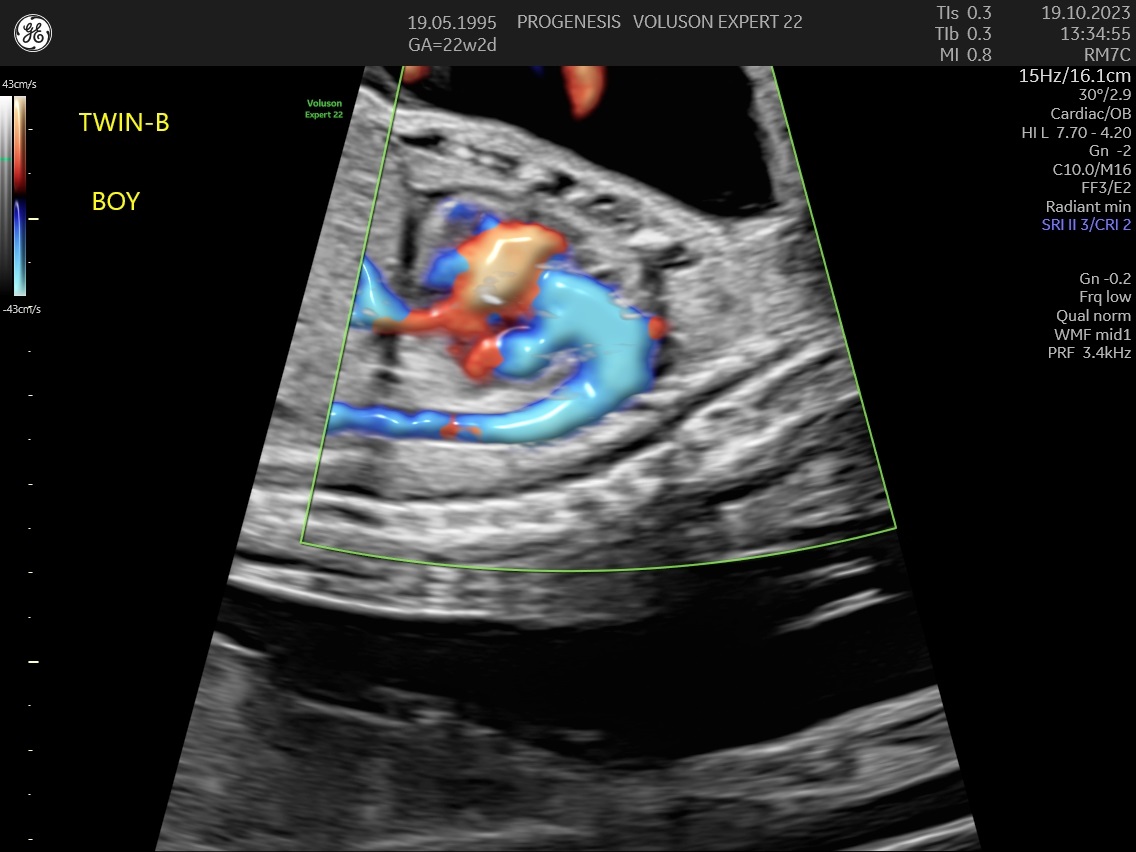

ε) Ο υπολογισμός της πιθανότητας προεκλαμψίας και ενδομήτριας καθυστέρησης της ανάπτυξης του εμβρύου.

Η μέτρηση των αντιστάσεων στις αρτηρίες της μήτρας, θα εντοπίσει τις μητέρες που έχουν αυξημένη πιθανότητα να εμφανίσουν υπέρταση ή προεκλαμψία στη κύηση ή και πλακουντιακή δυσλειτουργία που θα οδηγήσει σε ελλάτωση της εμβρυϊκής ανάπτυξης (μικρό έμβρυο).